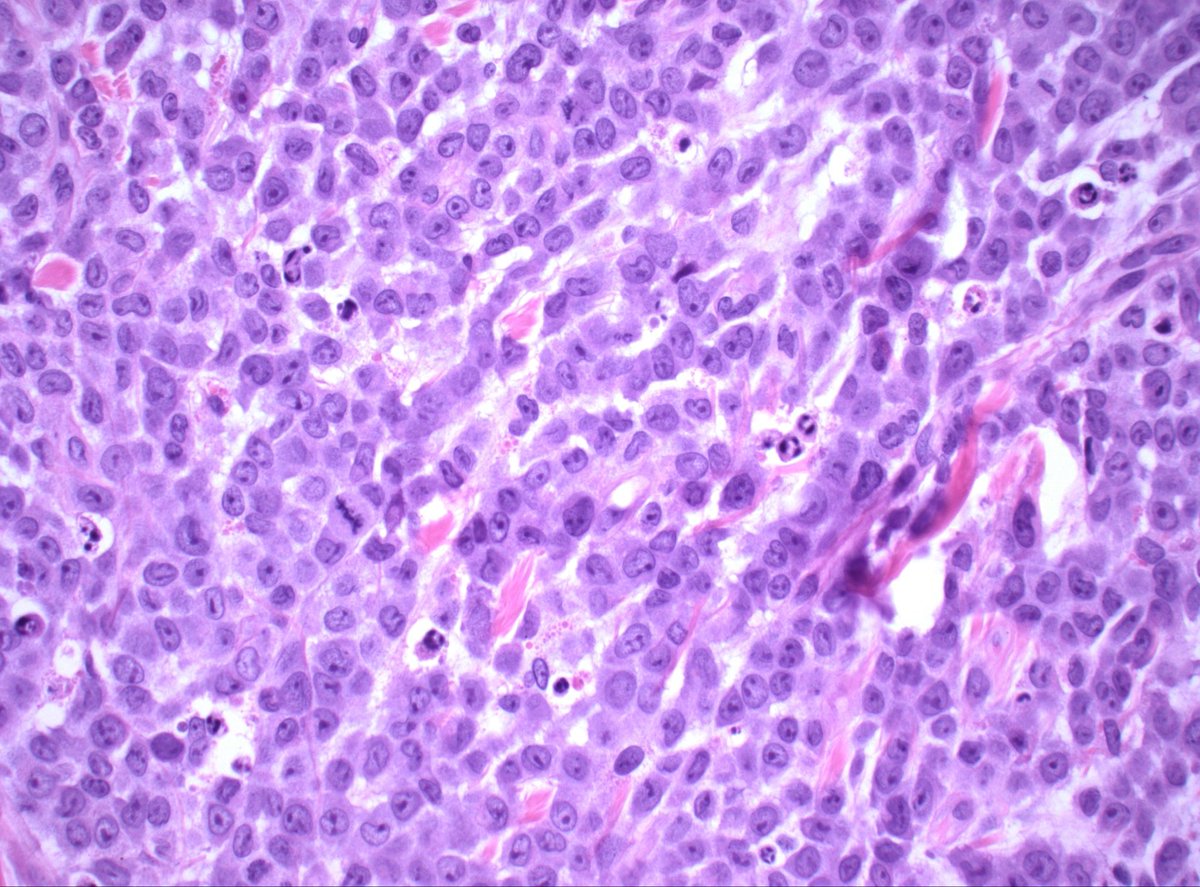

@MirunaPopescu13

DLBCL, NOS showing signet ring cell-like morphology. #hemepath #PathTwitter